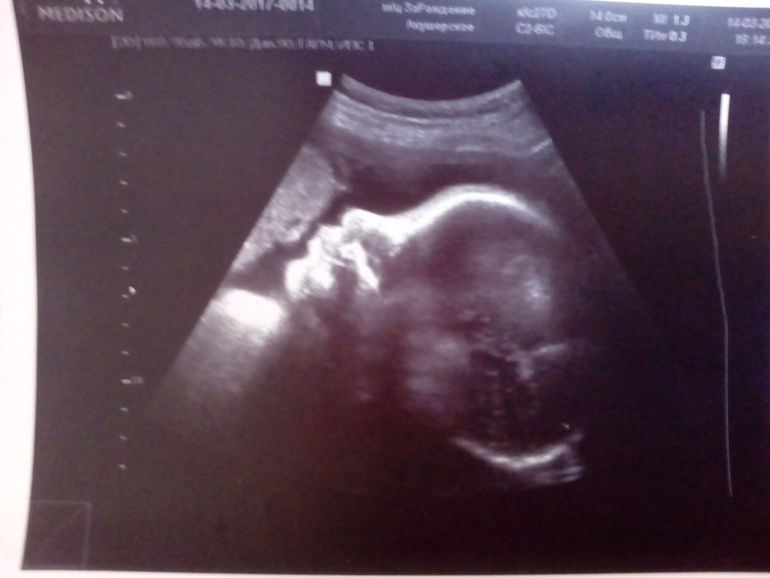

Пошла 34 неделя, а вчера мы прошли третий, последний скрининг) Ходили с мужем, он очень рад, ведь как нам сказали и показали, у нас сто процентный мальчишка, и мы можем не сомневаться) Всё у нас хорошо, развиваемся, весим 1900 кг. Правда ПДР сдвинулся с 3 мая на 11 мая, ну ничего)

Прибавила в весе с начала беременности 8 кг, думаю, вполне нормально, но тяжеловато немножко все же ходить. С прошлой недели поползли растяжки внизу живота, чего я очень не хотела(( Хочется поскорее родить и увидеть нашего малыша) А вот и мы))